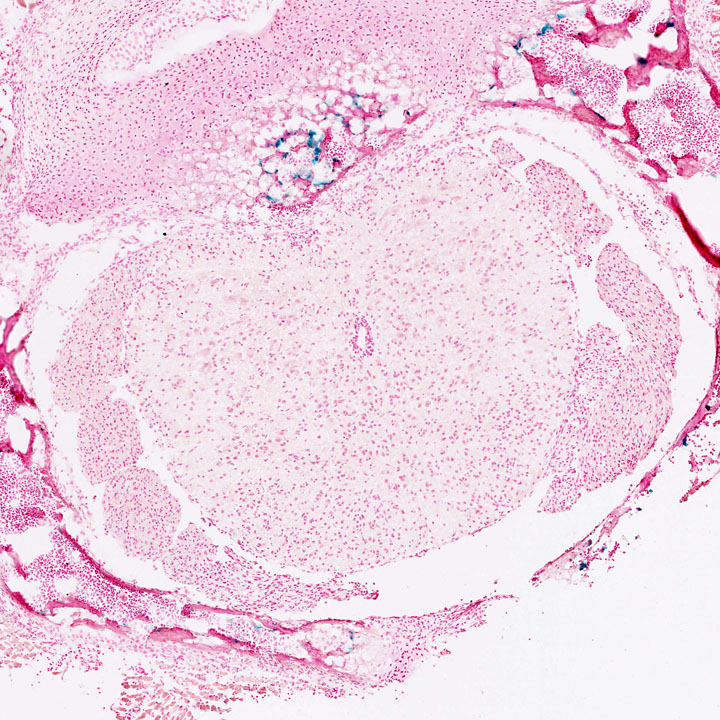

Nervous System